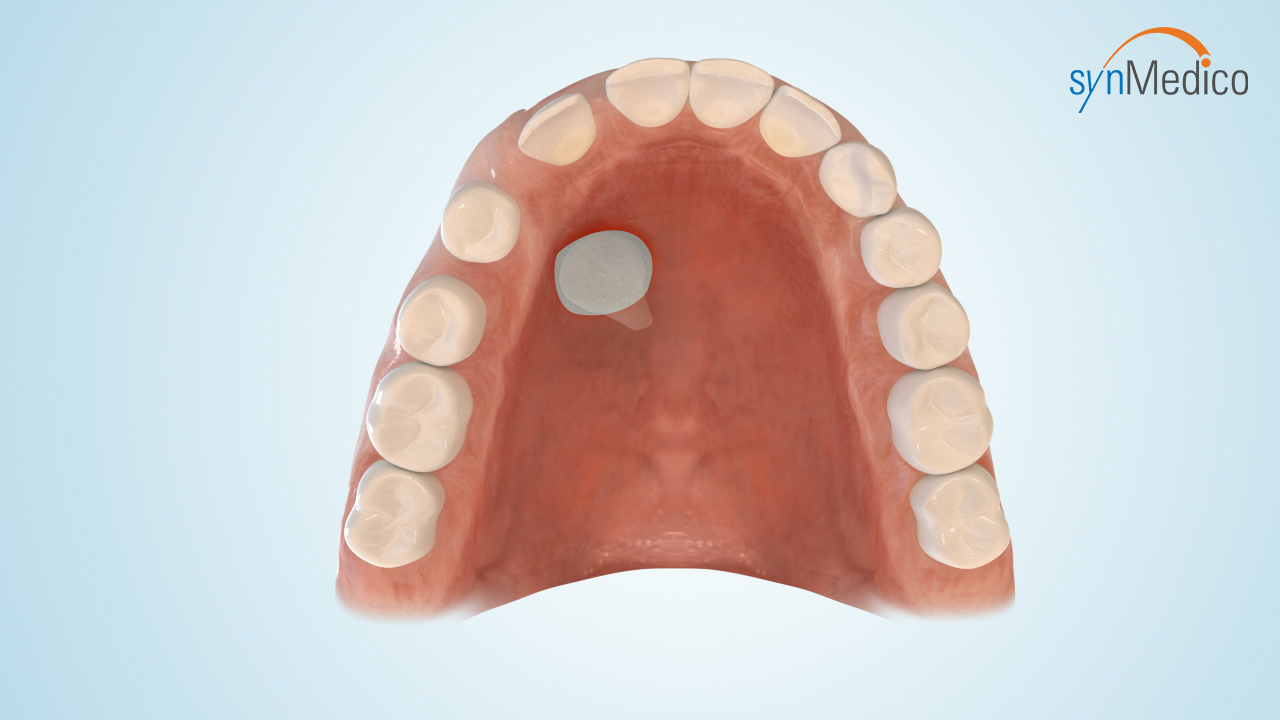

Freilegung von Zähnen

Gelegentlich verbleiben Zähne in der Wachstumsphase im Kiefer, da eine Blockade durch Nachbarzähne den Durchtritt verhindert. Durch eine kombinierte Behandlung mit den Techniken der Kieferorthopäde und der Kieferchirurgie können solche Zähne in die Zahnreihe eingestellt werden.